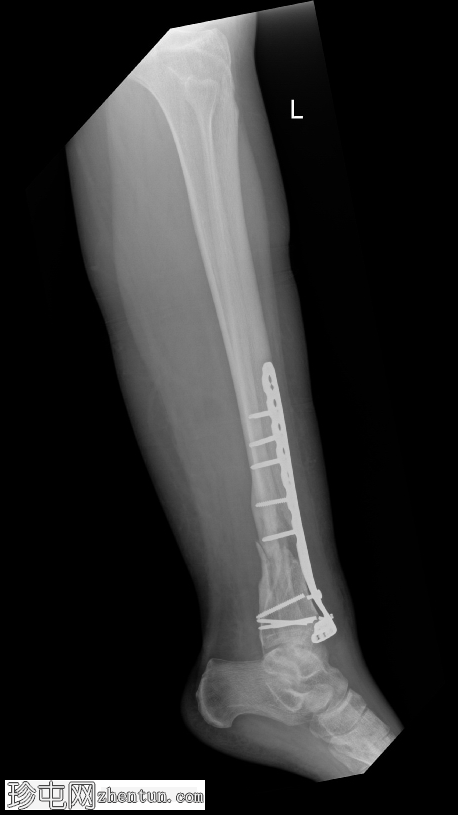

侧位片

2.png

正位片

可见胫骨远端前内侧支撑钢板,并有多枚螺钉固定,与既往胫骨远端骨折切开复位内固定术(ORIF)相符。

数枚远端螺钉断裂,钢板远端与胫骨远端骨膜表面分离,提示钢板与骨骼接触不良,可能存在内固定松动或部分机械失效。其余螺钉及钢板近端部分完整,对位良好。

胫骨远端内侧可见一小块骨化良好的骨碎片,密度与邻近骨皮质相似,提示为既往骨折残留碎片,而非急性骨折碎片。

骨折部位显示部分愈合,胫骨和腓骨整体对位良好。踝关节间隙保持正常。未发现新的骨折、脱位或骨膜反应。

无既往X线片可供对比。